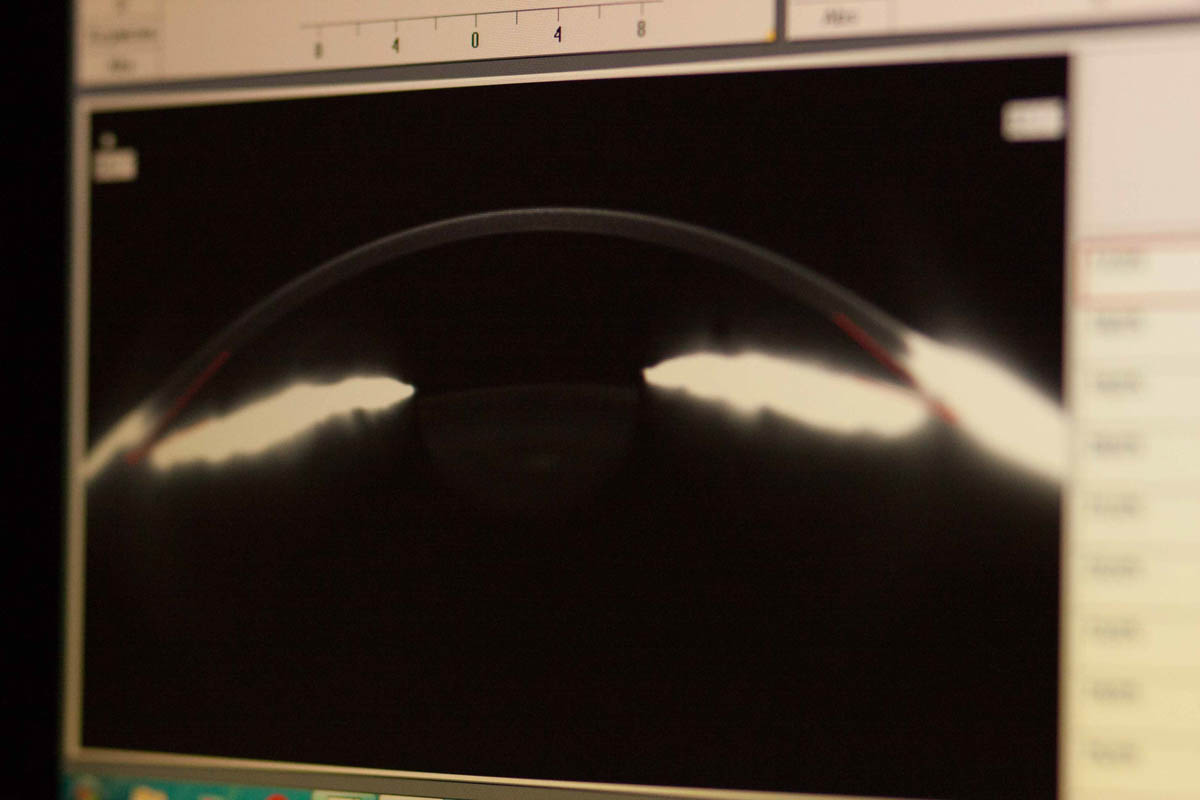

During this time, the cornea is shaped using a laser until the desired contour is achieved, allowing for proper light reflection and, as a result, perfect visual acuity.

If you’re curious about the permanent treatment options for astigmatism (laser vision correction) at Blikpol in the Tri-City area, click here: Laser vision correction. Learn more about laser treatment for astigmatism. We invite you for a consultation. If you experience spatial awareness issues, blurred vision, and a decrease in visual acuity, this may indicate an irregular corneal shape, and this visual impairment requires treatment. During an examination, the specialist will determine the type of astigmatism in your case (e.g., simple or reverse astigmatism). Using professional equipment like the Jawala oflalmometer, specialists can determine the curvature radius.

Our patients can also enjoy clear vision, so schedule a consultation and undergo astigmatism treatment as soon as possible. Whether you suffer from hyperopic astigmatism, myopic astigmatism, regular astigmatism, or mixed astigmatism caused by corneal and lens distortion, visit us and undergo professional eye exams. For astigmatism treatment, choose Blikpol! Our diagnostic methods include using a Lacido disk projected onto the corneal surface, which is then recorded by a camera. The results of the test include a corneal map and a corneal surface cross-section.